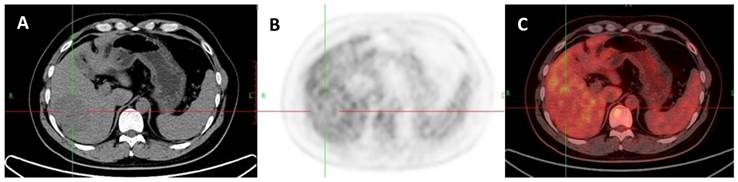

Figure 10

A 73-year-old man with a cholangiocarcinoma which was proved by liver biopsy. A: Axial non-contrast CT-scan showed a low density lesion in left lobe; B: 18FDG PET image showed higher uptake in the lesion compared to liver background (SUVratio=5.6); C: Axial 18FDG PET/CT fusion image.

The ROC curves and AUC of SUV ratio in younger group are shown in Figure 2. ROC analysis showed that the optimal cut-off value in these patients was 1.17 for SUV ratio and 0.962 for AUC. The younger patients group showed the highest sensitivity and specificity, followed by the older group, and the middle-aged group. Typical 18FDG-PET/CT imaging examples of benign and malignant solitary liver lesions in this group are displayed in Figure 3 and 4. Figure 3 showed a female patient with liver cyst where the SUV ratio was 0.3, and Figure 4 showed a male patient with HCC of which the SUV ratio was 2.1. The ROC curves and AUC of SUV ratio in middle-aged group are shown in Figure 5. ROC analysis showed that the optimal cut-off value in all patients was 1.45 for SUV ratio and 0.650 for AUC. The middle-aged group revealed the lowest sensitivity and specificity. Typical 18FDG-PET/CT imaging examples of benign and malignant solitary liver lesions in this group are displayed in Figure 6 and 7. In Figure 6 from a female patient with liver abscess, the SUV ratio was 4.1, which was much higher than the optimal cut-off value. On the other hand, in figure 7 from a male patient with HCC, the SUV ratio was only 0.98. The ROC curves and AUC of SUV ratio in elderly group are presented in Figure 8. ROC analysis showed that the optimal cut-off value in these patients was 1.25 for SUV ratio and 0.973 for AUC. The elderly group yielded relatively high sensitivity and specificity. Typical 18FDG-PET/CT imaging examples from a patient with benign and malignant solitary liver lesions in this group are demonstrated in Figure 9 and 10, respectively.